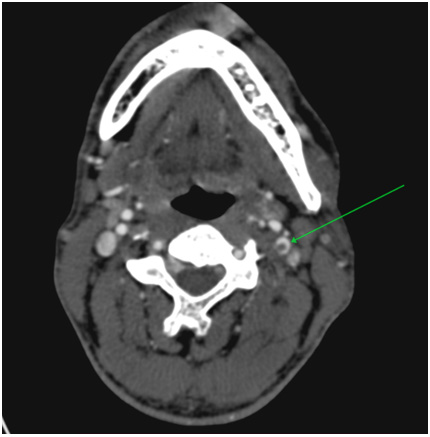

Via native and contrast CT scan intracranial hemorrhage was excluded and the contrast CT scan revealed a thrombus in the left internal carotid artery (Figure 1&2). Doppler ultrasound was also performed which showed a carotid stenosis, caused by a mural thrombus (Figure 3). Treatment with tissue plasminogen activator Actilyse was initiated. The total dose was 63 mg, 6 mg of which administered as a bolus i.v. injection and the remaining 57 mg were given as a continuous infusion for one hour. In the next 24 hours the patient received a heparin infusion, according to the aPTT values.